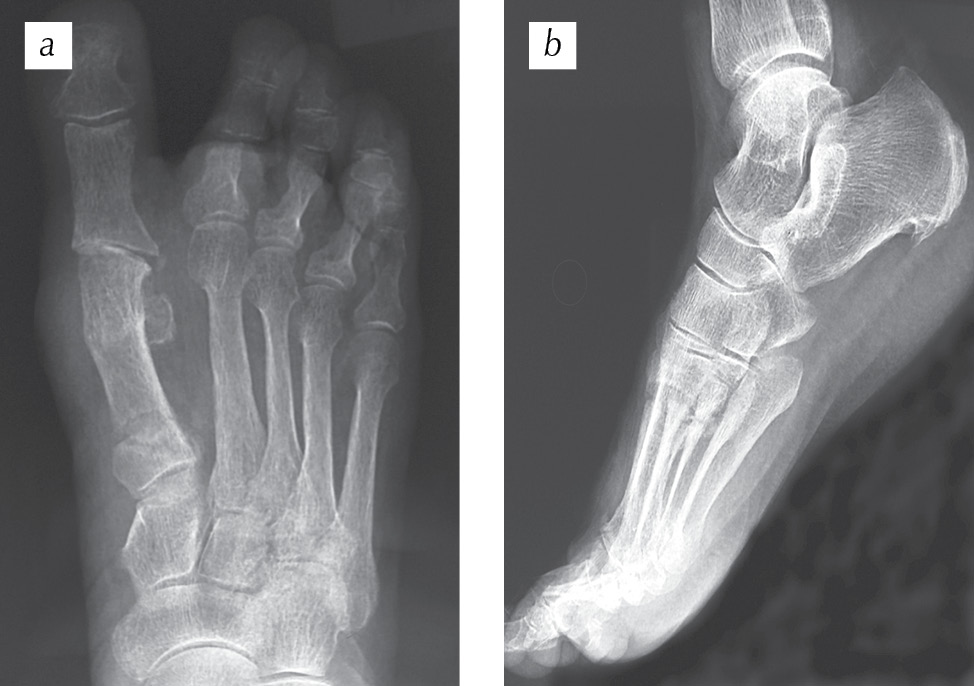

Пациентка Е., 73 года, поступила в отделение травматологии и ортопедии Покровской больницы в плановом порядке с жалобами на деформацию правой стопы, боль при ходьбе (рис. 1). Со слов пациентки, боль, дискомфорт в области правой стопы беспокоят в течение многих лет. В последние два года отмечала выраженные проблемы с ношением и подбором обуви. После обследования установлен диагноз: «Поперечное плоскостопие: hallux valgus правой стопы. Молоткообразная деформация II пальца правой стопы». На рис. 2 представлены рентгенограммы пациентки до оперативного лечения. Угол вальгусного отклонения I пальца, образованный осями I плюсневой кости и проксимальной фаланги I пальца, равен 40° при норме 8–16°. Межфаланговый угол I пальца, образованный осями проксимальной и дистальной фаланг I пальца, равен 0° при норме 0–8°. Угол варусного отклонения I плюсневой кости, образованный осями I и II плюсневых костей, составил 23° при норме 5–14°. Угол наклона суставной поверхности головки I плюсневой кости, образованный осью I плюсневой кости и осью, проведенной перпендикулярно линии, соединяющей края суставной поверхности головки I плюсневой кости, равен 20° при норме 3–10°. Угол наклона суставной поверхности основной фаланги к ее оси, образованный проксимальной фалангой I пальца и перпендикуляром к плоскости суставной поверхности этой же фаланги, равен 3° при норме 0–5°. Угол наклона суставной поверхности медиального плюснеклиновидного сустава, определяемый как угол между линией данного сустава и перпендикуляром к тангете медиального края медиальной клиновидной кости, равен 20° при норме 0–20°.

Рис. 1. Рентгенограммы пациентки Е. до оперативного лечения (выраженный костно-хрящевой экзостоз головки I плюсневой кости, вальгусная деформация I пальца, молоткообразная деформация II пальца с омозолелостью на тыле проксимального межфалангового сустава)

Fig. 1. Radiographs of patient E. before surgical treatment (pronounced bone-cartilage exostosis of the head of I metatarsal bone, valgus deformity of the first toe, hammer-like deformity of the second toe with homosoleness on the back of the proximal interphalangeal joint)

Рис. 2. Рентгенограммы переднего отдела правой стопы пациентки Е. до оперативного лечения: а — прямая проекция; b — косая (3/4) проекция (пояснения см. в тексте)

Fig. 2. Radiographs of the anterior part of the right foot of patient E. before surgery: a — straight projection; b — oblique (3/4) projection (see the text for explanations)